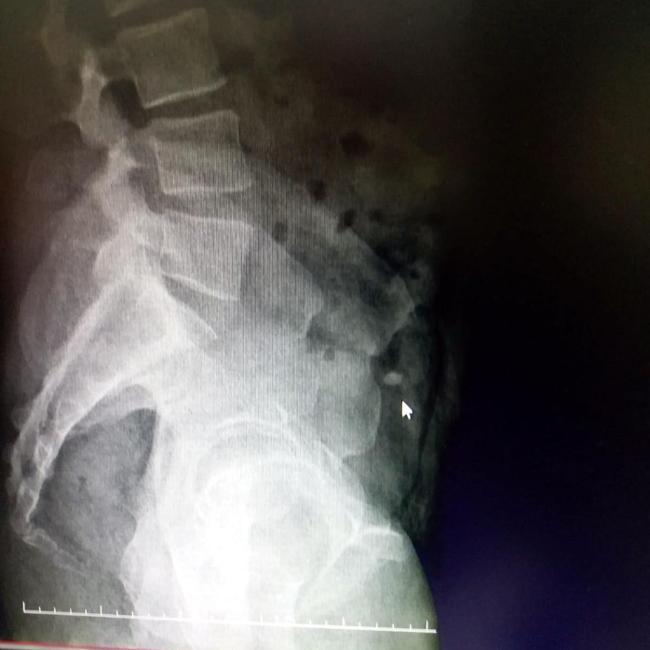

The 54-year-old tourist denied any wrongdoing but security camera footage and x-ray scans confirmed the jeweler's claim.

Police took the man to a hospital where he was given food and laxatives on Oct. 4.